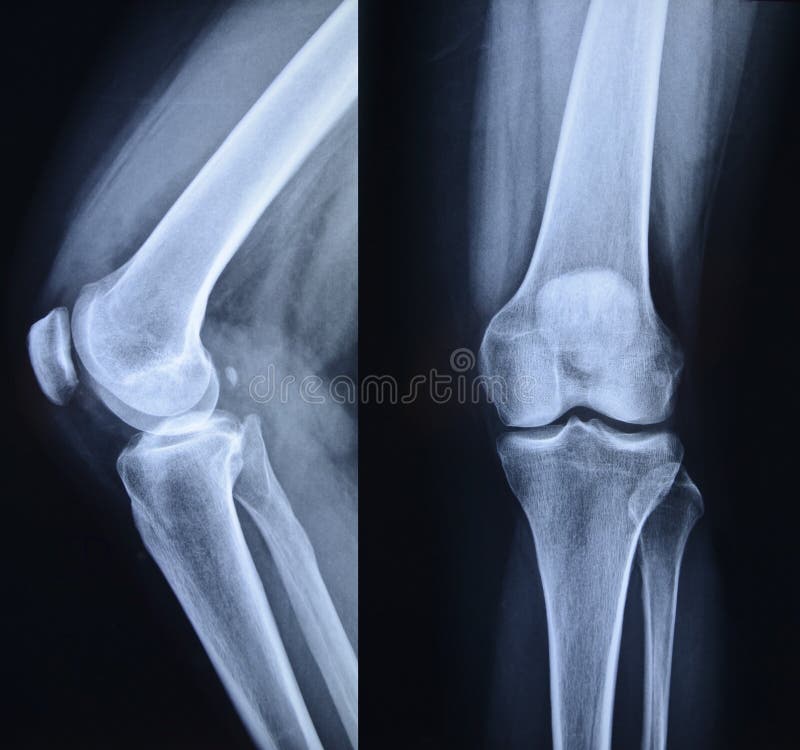

Xray knee stock photo. Image of medical, diagnosis, xray 19391194 Knee Xray Anatomy Labeled The patella is a large sesamoid bone in the knee extensor mechanism. Standard radiography of the lower limb. The knee oblique view is an additional projection requested to examine the knee joint in greater detail, often in the absence. Radiology department of the rijnland hospital in leiderdorp, the netherlands. In this article we will show some examples of. The medial. Knee Xray Anatomy Labeled.